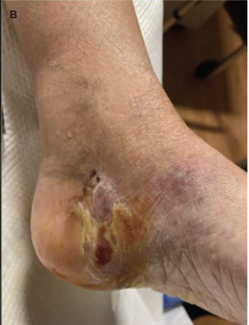

Stephanie Behme, DPM; Shiwei Zhou, MD; Andrew Brown, DPM; Gary M. Rothenberg, DPM

A 64-year-old female presented with an enlarging ulceration that failed to respond to antibiotic therapy based on routine aerobic culture results. Acid-fast bacilli (AFB) cultures revealed a nontuberculous mycobacteria infection with...